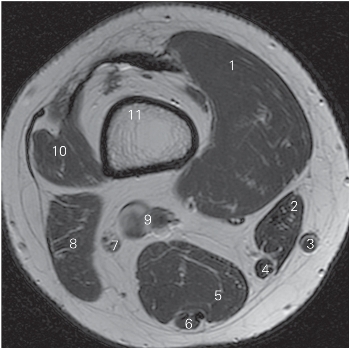

图5-13 经股骨下份的横断层MR T1加权图像

1 股内侧肌 vastus medialis 2 缝匠肌 sartorius

3 大隐静脉 great saphenous vein 4 股薄肌腱 tendon of gracilis

5 半膜肌 semimembranosus 6 半腱肌 semitendinosus

7 胫神经 tibial nerve 8 股二头肌 biceps femoris

9 腘动、静脉 popliteal artery and vein

10 股外侧肌 vastus lateralis

11 股骨 femur